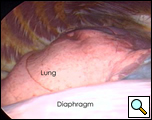

In the operating room, under general anesthesia and one lung ventilation, the thoracoscope was introduced at the right midaxillary line and the 7th intercostal space (Video 1 below). The cyst was readily visualized at the anterolateral aspect of the right pericardium, measuring approximately 9x6cm (Figure 3). The phrenic nerve was seen posterior to the cyst. The second incision was made at the anterior axillary line in the 4th intercostal space. A ring clamp was used to grasp the cyst (Figure 4). The third incision was made at the scapula line in the 5th intercostal space. Thoracoscopic scissors and cautery (at a low setting to minimize the chance of cardiac arrhythmias) were used through that port to dissect the cyst from the pericardium (Figure 5). The connection between the cyst and the pericardial space was identified. It was small, and was divided with the scissors. The dissection of the posterior aspect of the cyst completed the removal. The phrenic nerve was clearly visualized at all times. The pathology report confirmed the diagnosis of a benign mesothelial-lined cyst (Figure 6).

| Figure 3.: Intraoperative view of pericardial cyst. | Figure 4. Ring clamp retraction of pericardial cyst. |